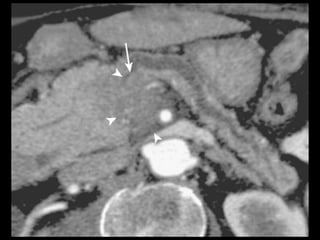

Hemorragia

Artéria esplênica e seus ramos e artérias das

arcadas pancreaticoduodenais.

TC: líquido com alta atenuação na cavidade

peritoneal ou no retroperitônio, numa coleção

líquida preexistente ou num pseudocisto;

Tratamento: angiografia de emergência, com

embolização seletiva.